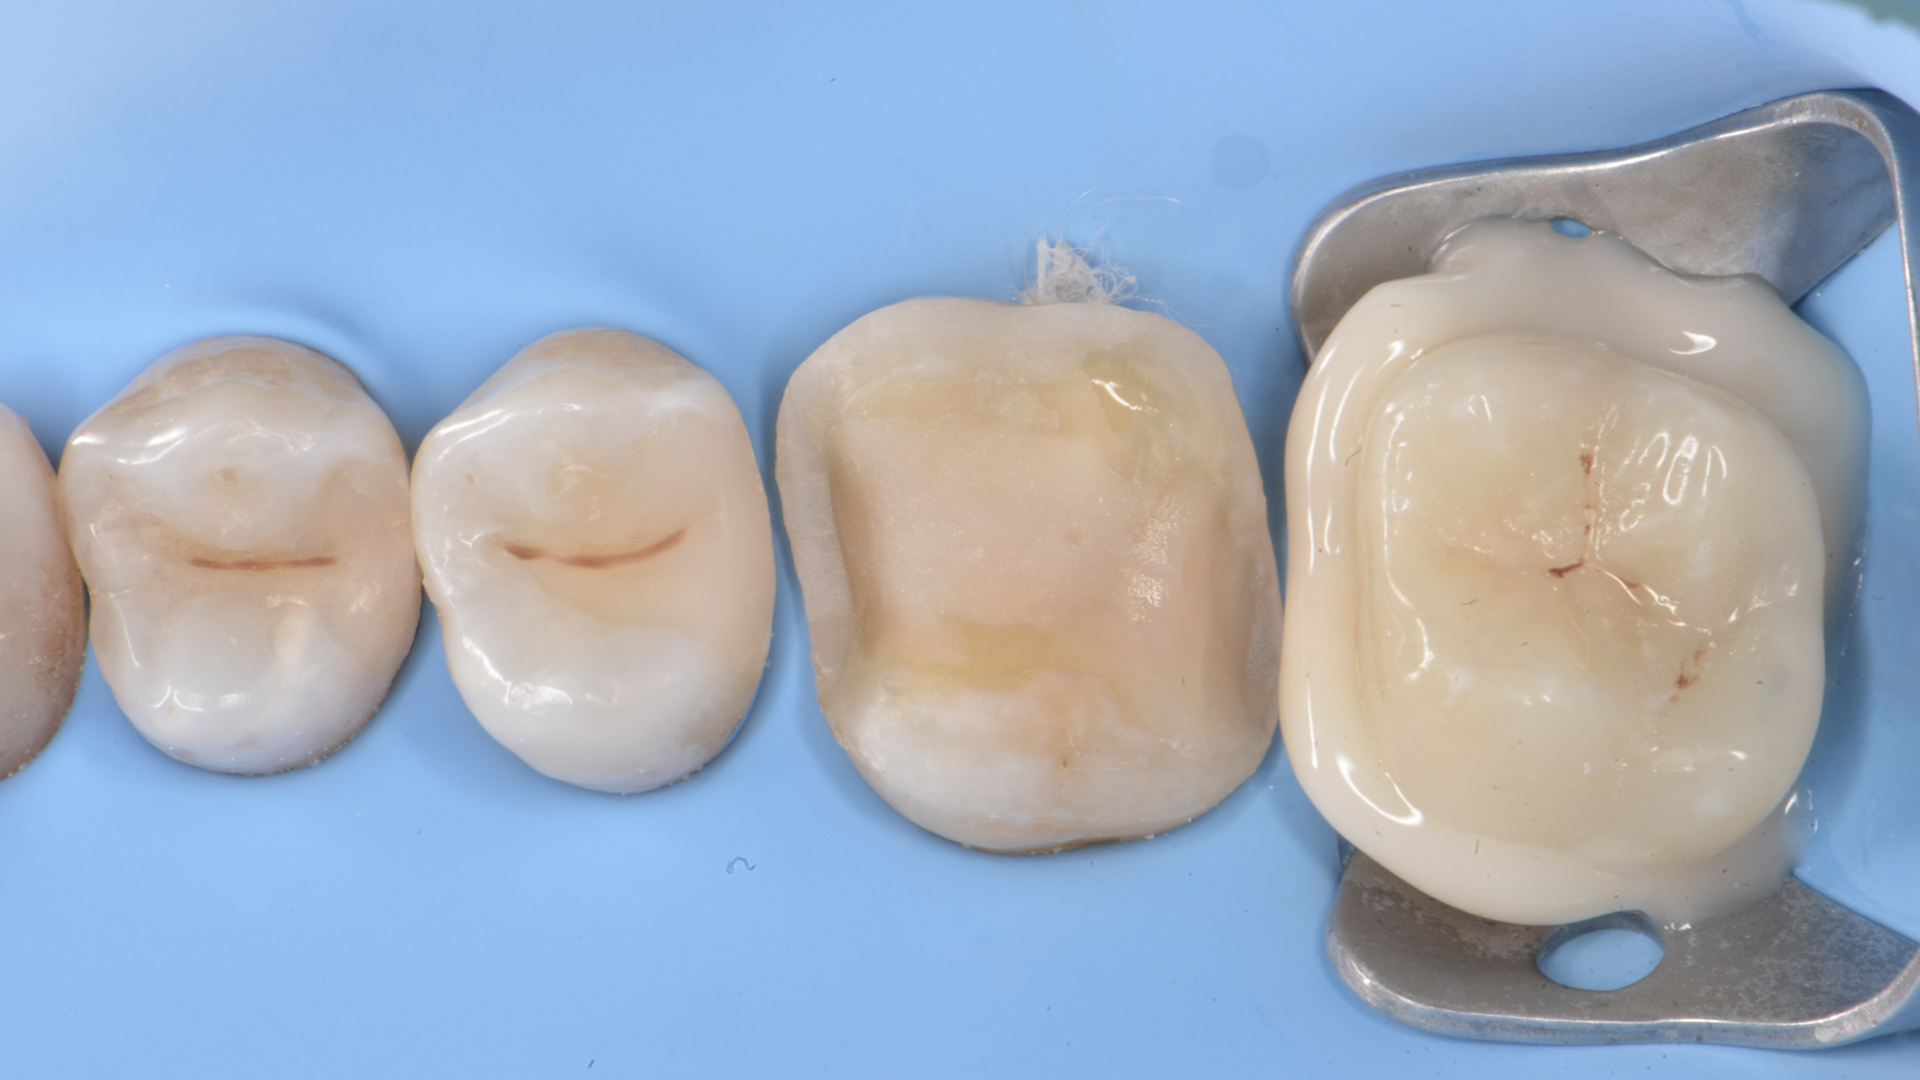

Figure 1. Preoperative situation. Occlusal view (Rx above)Figure 2. Isolation with rubber dam of the operative area

Figure 5. Restoration of distal wall 1.5 (Garrison Composi-tight 3D Fusion System)Figure 6.  Restoration 1.4-1.5 completed. Final Preparations 1.6 -1.7